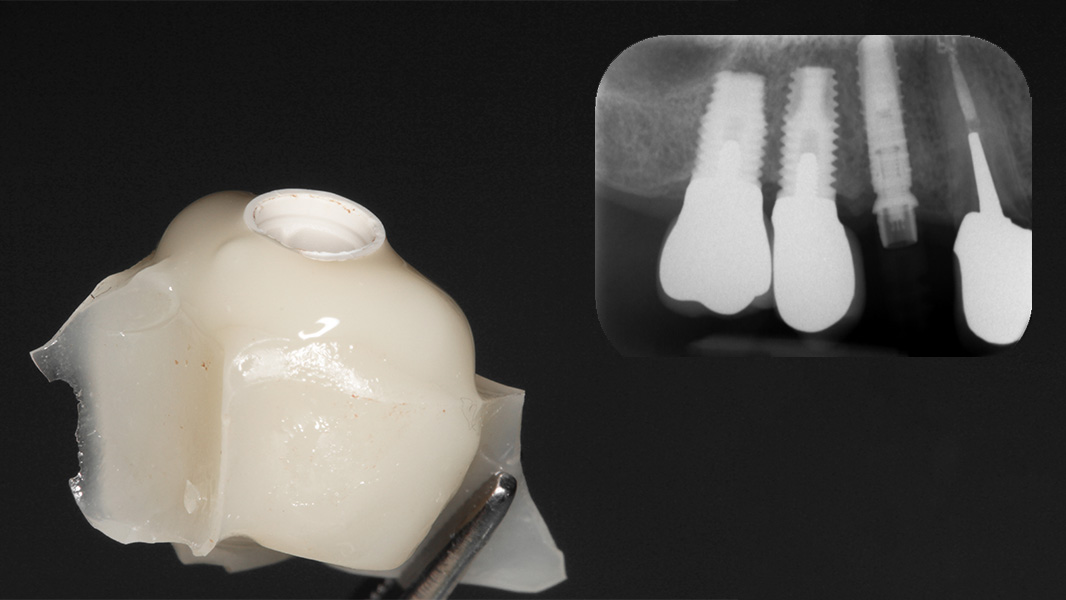

iSy Implantat mit vormontierter Implantatbasis

Bei der transgingivalen Einheilung ist iSy leicht und zeitsparend zu handhaben, denn iSy kommt mit allem, was Sie brauchen. Im Set sind neben den Implantaten mit vormontierter Implantatbasis ein Einpatienten-Formbohrer, Gingivaformer und Multifunktionskappen enthalten. Durch Klicken wird sowohl der Gingivaformer als auch die Multifunktionskappe sowie die temporäre Versorgung direkt auf der Implantatbasis rotationsgesichert platziert. Klicken statt Schrauben – spart Zeit im Behandlungsabflauf.

Nicht nur die korrekte dreidimensionale Positionierung der Implantate, sondern auch das Know-how der Knochenaugmentation und die entsprechende Manipulation des Weichgewebes sind essenziell für den Erfolg. Die Kieferknochenrekonstruktion mit autologen Knochenblöcken, die nach der Beschreibung von Prof. Dr. F. Khoury ausgedünnt werden, sowie das Auffüllen der entstandenen Hohlräume mit autologen Knochenspänen führen zu einem vorhersagbaren, langzeitstabilen laminären Knochen. Auch das Implantatdesign mit der parallelwandigen Schulter sowie das Platform-Switching tragen maßgeblich zur erfolgreichen Rekonstruktion bei. Ein weiterer Vorteil des iSy Implantatkonzepts ist die Implantatbasis. Bei transgingivaler Einheilung verbleibt sie bis zur endgültigen Versorgung auf dem Implantat. Die Manipulation des Weichgewebes durch häufigen Abutmentwechsel hat laut Studien einen beachtlichen Anteil an Knochen- und Weichgewebsveränderungen. Auch bei gedeckter Einheilung werden ab dem Zeitpunkt der Freilegung mithilfe der Implantatbasis Abutmentwechsel minimiert.